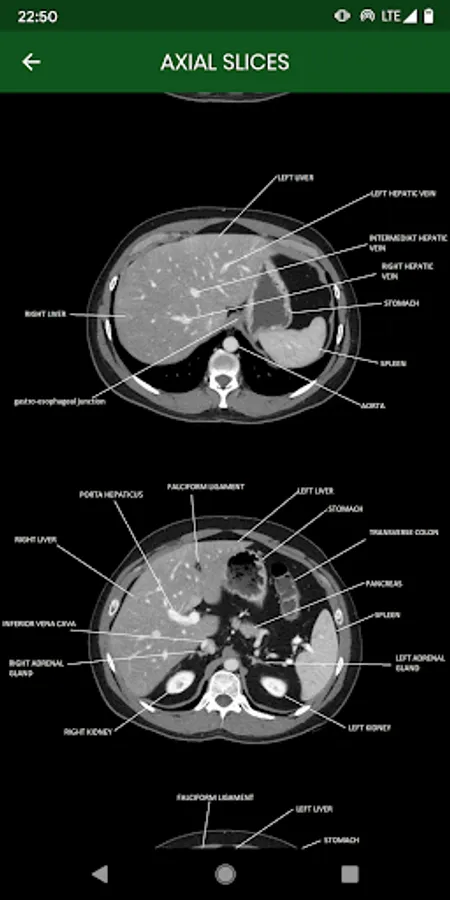

abdominal CT: annotated slices

this app is made for educational purpose. it will help beginners to recognize the normal anatomy of the abdomen examined in CT

abdominal CT: annotated slices Screenshots